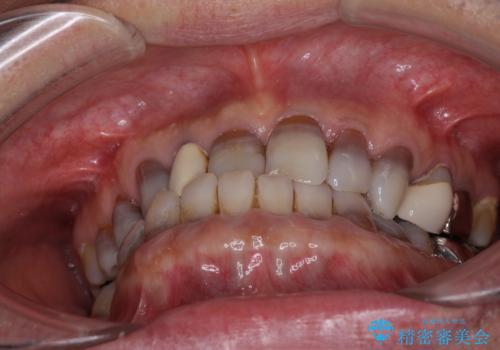

- 前歯のクロスバイトを気にして来院された患者様です。

骨格的に下顎が前方位ではありますが、歯並びが改善されれば正常咬合となることが分かったため、インビザラインを用いて咬み合わせを改善していくこととしました。